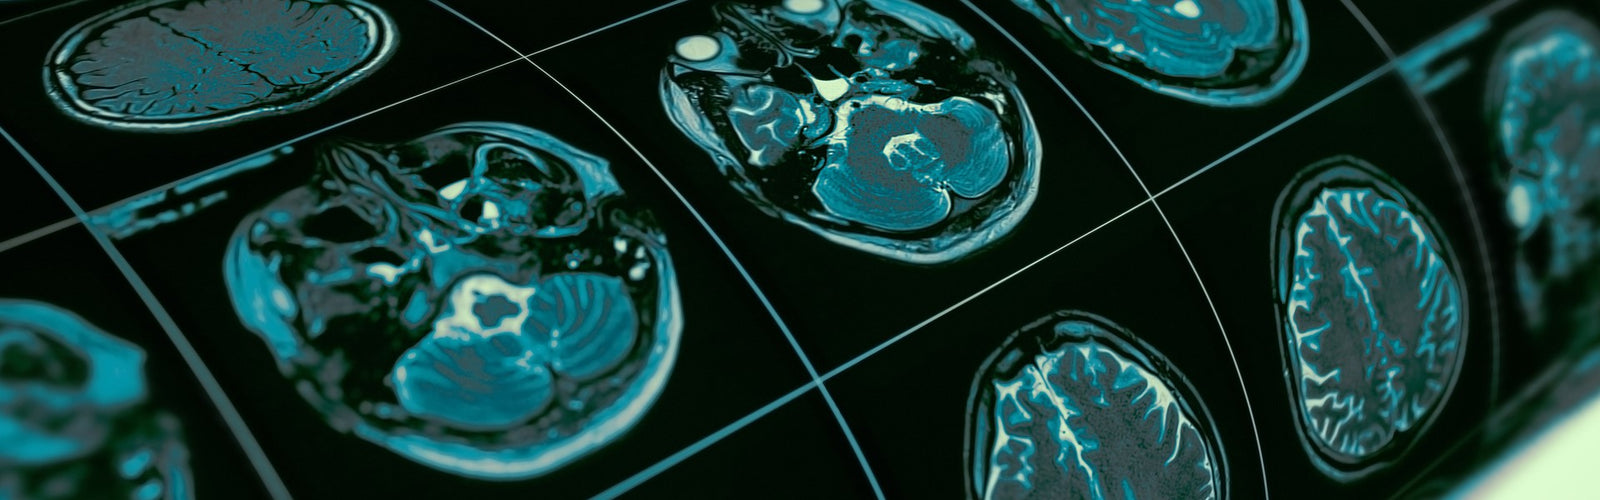

When blood flow to some parts of the brain gets blocked or slowed down, it triggers a medical condition known as vascular dementia. The state declines a person’s ability to think due to reduced oxygen and nutrients. As the brain cells in the affected regions continue to die due to the deprivation, so does one's thinking ability. The thinking difficulties manifested in vascular dementia may occur suddenly after a stroke or may happen gradually and worsen over time.

All parts of your body require a sufficient flow of blood to sustain the life of different cells. However, brain cells are the most vulnerable regarding inadequate blood flow. When blood is blocked from reaching these cells, it causes a shortage of nutrients and oxygen, hence the cells' death. The result is a decline in a person’s thinking skills.